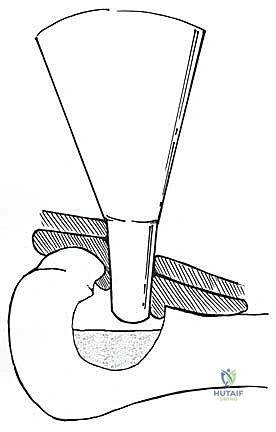

Following the final thaw and lavage, the cavity is meticulously dried. The bone is now structurally compromised and functionally dead. Reconstruction is mandatory. The cavity is typically packed with PMMA bone cement. The cement is pressurized into the cancellous interstices, providing immediate structural support and acting as a secondary thermal and chemical adjuvant.

Preparation for reconstruction: The ablated cavity is ready to receive PMMA or structural bone graft.

Application of PMMA bone cement into the defect, providing immediate structural stability and a radiopaque background.

If the subchondral plate is paper-thin, a layer of cancellous or structural allograft/autograft may be placed against the cartilage before cementing to prevent thermal injury to the joint from the exothermic curing of the PMMA. Finally, to bypass the stress risers of the cortical window and the necrotic bone segment, rigid internal fixation is applied. This usually involves locking plates spanning the defect.